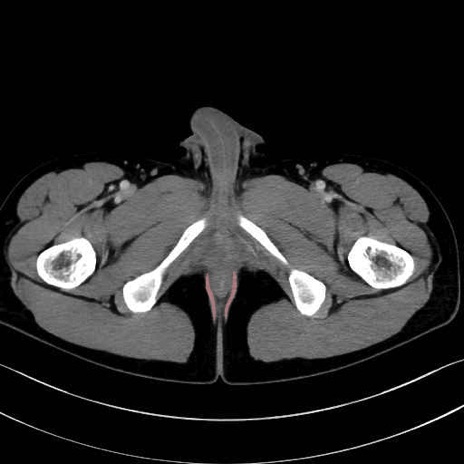

肛門挙筋(levator ani muscle)のCT画像の解剖

肛門挙筋 (Levator ani)